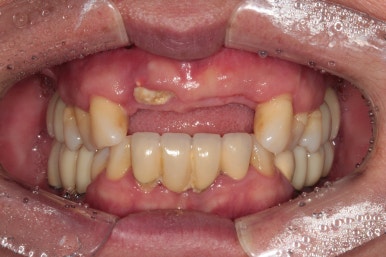

50대 여자 환자분입니다. 처음에 내원하셨을 때 정면 사진이에요.

딱 보아도 잇몸 상태가 참 좋지 않았습니다. ㅠㅠ 특히 위 앞니는 가만히 있어도 고름이 나오고 있는 상태지요..

우측 가쪽 앞니 (측절치)에서 active하게 농양이 나오고 있는 것을 보실 수 있어요.

당연히 위턱 앞니들이 모두 흔들흔들 합니다.

어금니는 임플란트로 치료를 받으셨지만, 앞니는 틀니를 해야한다는 말에 치과 방문을 미루고 미루시다가 소문을 듣고 저희 치과를 방문해주신 경우였어요..!